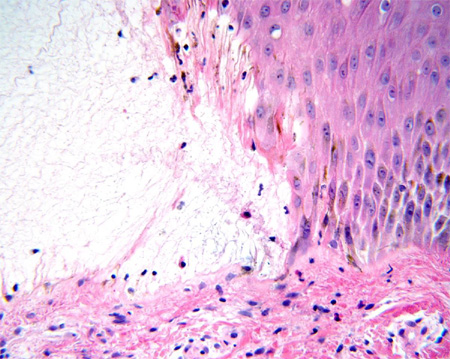

Буллезный пемфигоид

В полости пузыря имеется сеть фибрина, в то время как дермальный инфильтрат содержит большое количество эозинофилов

Из коллекции д-ра Весны Петрон-Росик (Dr Vesna Petronic-Rosic)